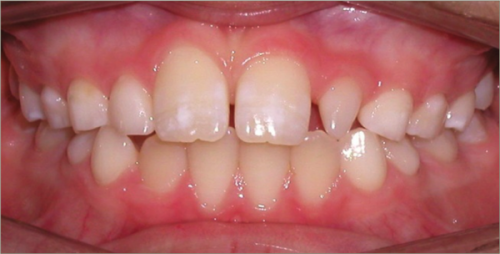

12 year old female:

Diagnosis:

- Missing upper right lateral incisor & lower right cuspid

- Horizontally impacted lower left cuspid

- Peg shaped upper left lateral incisor

Treatment:

- Extraction of impacted lower left cuspid, and peg shaped upper left lateral incisor

- Upper cuspids substituted as laterals

- Full fixed appliances

- 20 months